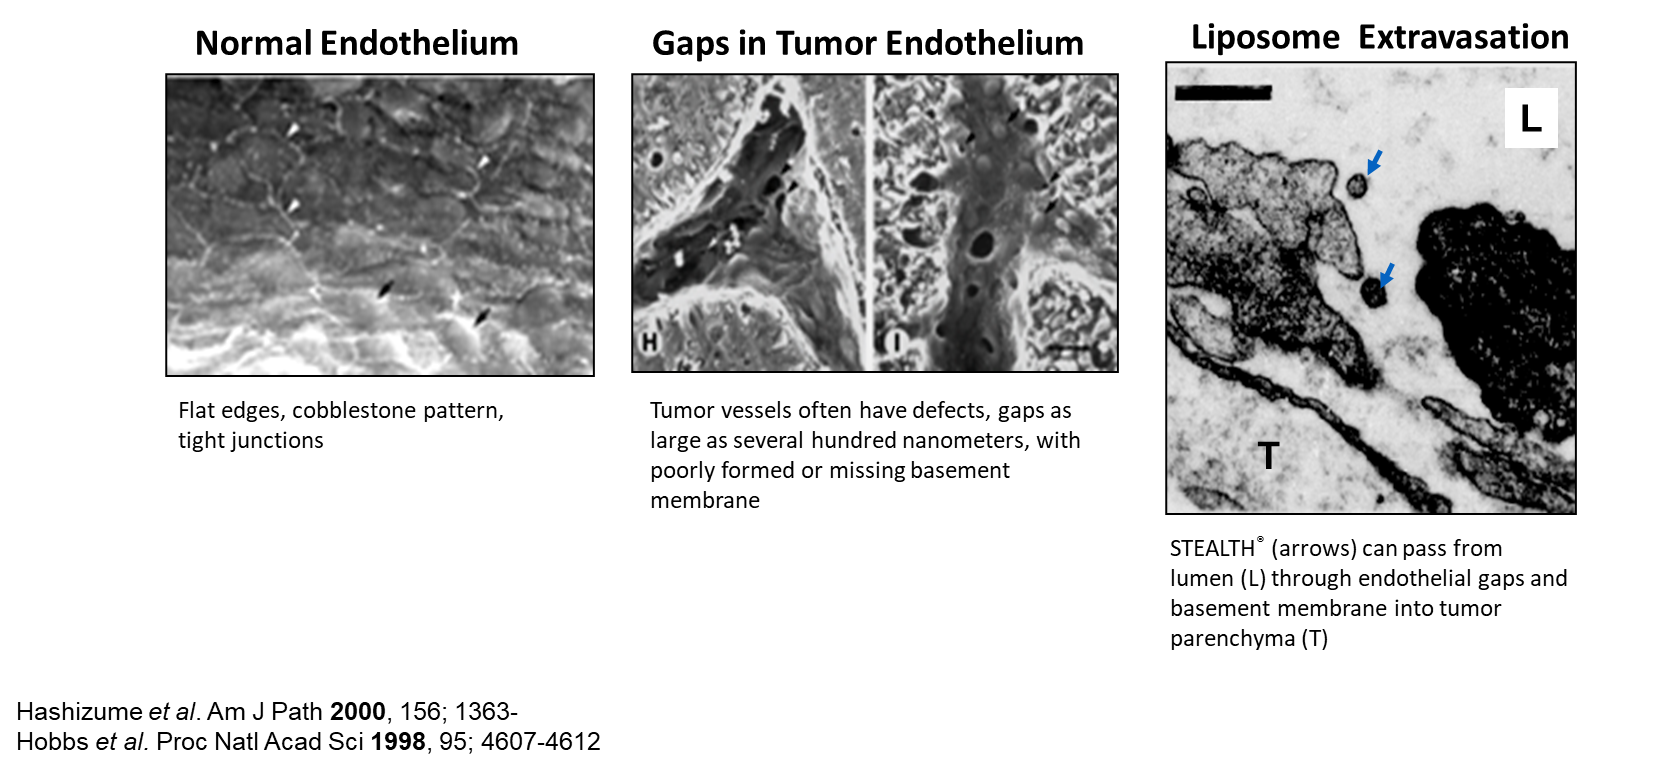

qTumours have Enhanced Permeability and Retention (EPR) effect compared to normal tissues due to the impaired lymphatic drainage in tumors.

qEnhanced permeability of tumor vessels

ØAngiogenesis

ØIncomplete formation of vessel walls and basement membrane

ØGaps and defects in endothelium

qEnhanced retention because of deficient lymphatic drainage

qLiposomes which are coated with polyethylene glycol will have higher hydrophilicity of their surfaces and hence less opsonization and subsequently lower RES-mediated clearance.

qThis means longer circulation time of the liposomes (encapsulating the anticancer drug) and subsequently higher chances of liposome extravasation into tumour cells.

qLong-circulating liposomes encapsulating anticancer drug (e.g. doxorubicin) may extravasate and accumulate in the tumour interstitium.